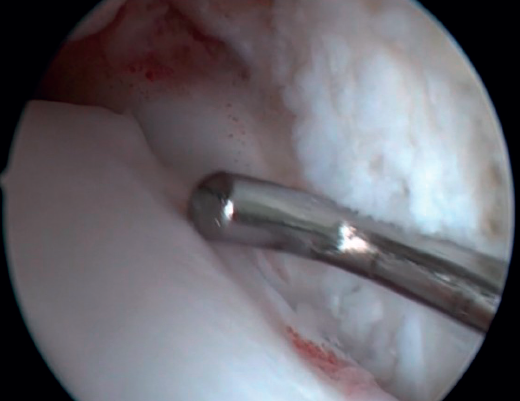

The confirmation of AAI is made by direct vision during arthroscopic examination (Figure 4). This technique allows us to visualise the entire joint, assess the state of the articular cartilage and ligaments, detect the presence of capsular adhesions, synovitis, synovial thickening, loose bodies, etc. It also allows us to carry out functional tests to reveal possible associated instabilities or to assess how the soft tissues causing pain suffer impingement. In our experience, the presence of ATFL lesions is very frequent.

Bassett's ligament should be preserved as long as it does not have a pathological appearance, ruling out thickening, partial tears or reciprocal lesions on the anterolateral surface of the talus (Figure 6), which are associated with anterolateral or rotational instabilities. The peroneal insertion is used as a reference to locate the distal insertion of the ATFL. The deltoid ligament at the medial groove should be inspected if associated rotational instability is suspected. During arthroscopy, direct ligament repair can be performed using sutures and anchors.